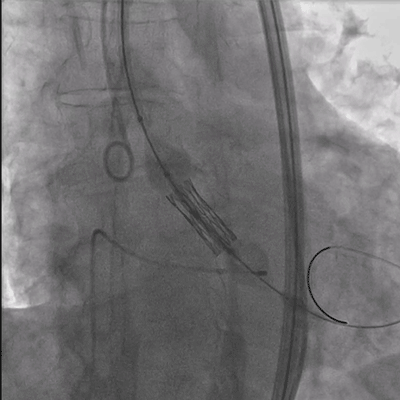

如下图所示,取得了极其满意的效果。

瓣膜释放

瓣膜释放后造影